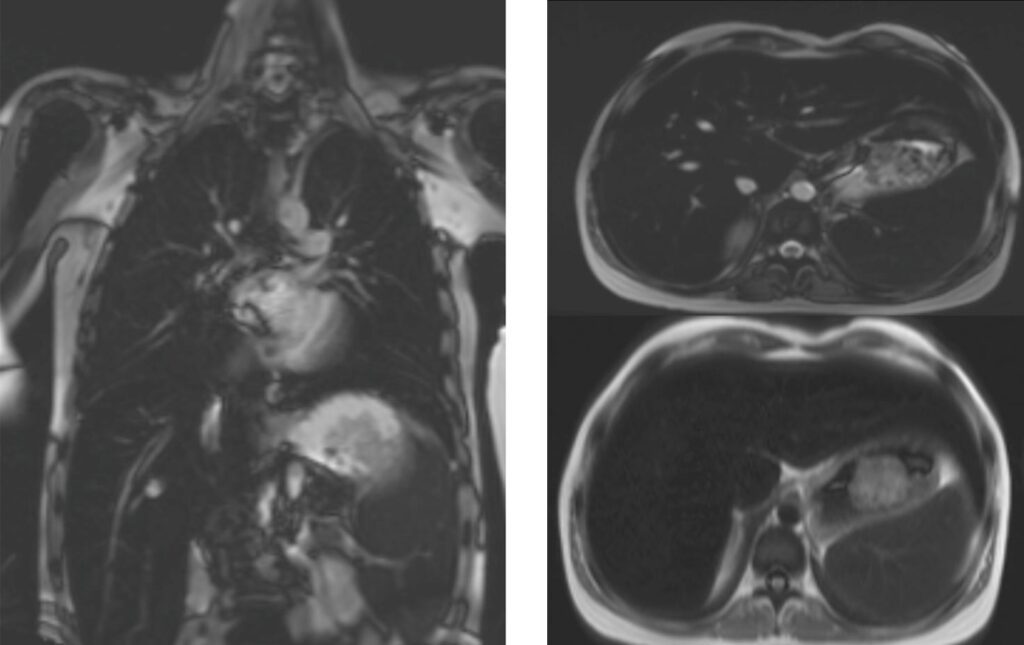

Se deriva a resonancia magnética cardiaca sin contraste ese mismo mes (protocolo de T2*) para evaluación de sobrecarga de hierro hepática y cardiaca, donde se evidencia lo siguiente:

Hepatoesplenomegalia, con medida máxima del bazo, diámetro anteroposterior en vista coronal y sagital 15 cm x 13 cm. Visualmente, sobrecarga severa de hierro en el hígado. El bazo también se observa oscuro, lo que sugiere sobrecarga de hierro. No hay evidencia de hematopoyesis extramedular paravertebral (Imagen 1). Dimensiones normales de grandes vasos.

Imagen 1

Las secuencias de movimiento cine SSFP demuestran función ventricular izquierda conservada (LVEF: 78%, MAPSE: 15 mm) sin alteración de la motilidad regional de las paredes de VI. Grosor normal de pared de VI (7mm). Tamaño normal y función conservada de ventrículo derecho. No valvulopatías